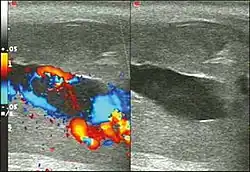

Color Doppler ultrasound demonstrating a hypoechoic collection that corresponds to hematoma with arteriovenous fistula secondary to traumatic injury of the penis due to impact with bicycle handlebars, resulting in high-flow priapism[11]

Penile ultrasonography with Doppler is the imaging method of choice, because it is noninvasive, widely available, and highly sensitive. By means of this method, it is possible to diagnose priapism and differentiate between its low- and high-flow forms.[11]

In low-flow (ischemic) priapism the flow in the cavernous arteries is reduced or absent. As the condition progresses, there is an increase in echogenicity of the corpora cavernosa, attributed to tissue edema. Eventually, changes in the echotexture of the corpora cavernosa can be observed due to the fibrotic transformation generated by tissue anoxia.[11]

In high-flow priapism normal or increased, turbulent blood flow in the cavernous arteries is seen. The area surrounding the fistula presents a hypoechoic, irregular lesion in the cavernous tissue.[11]